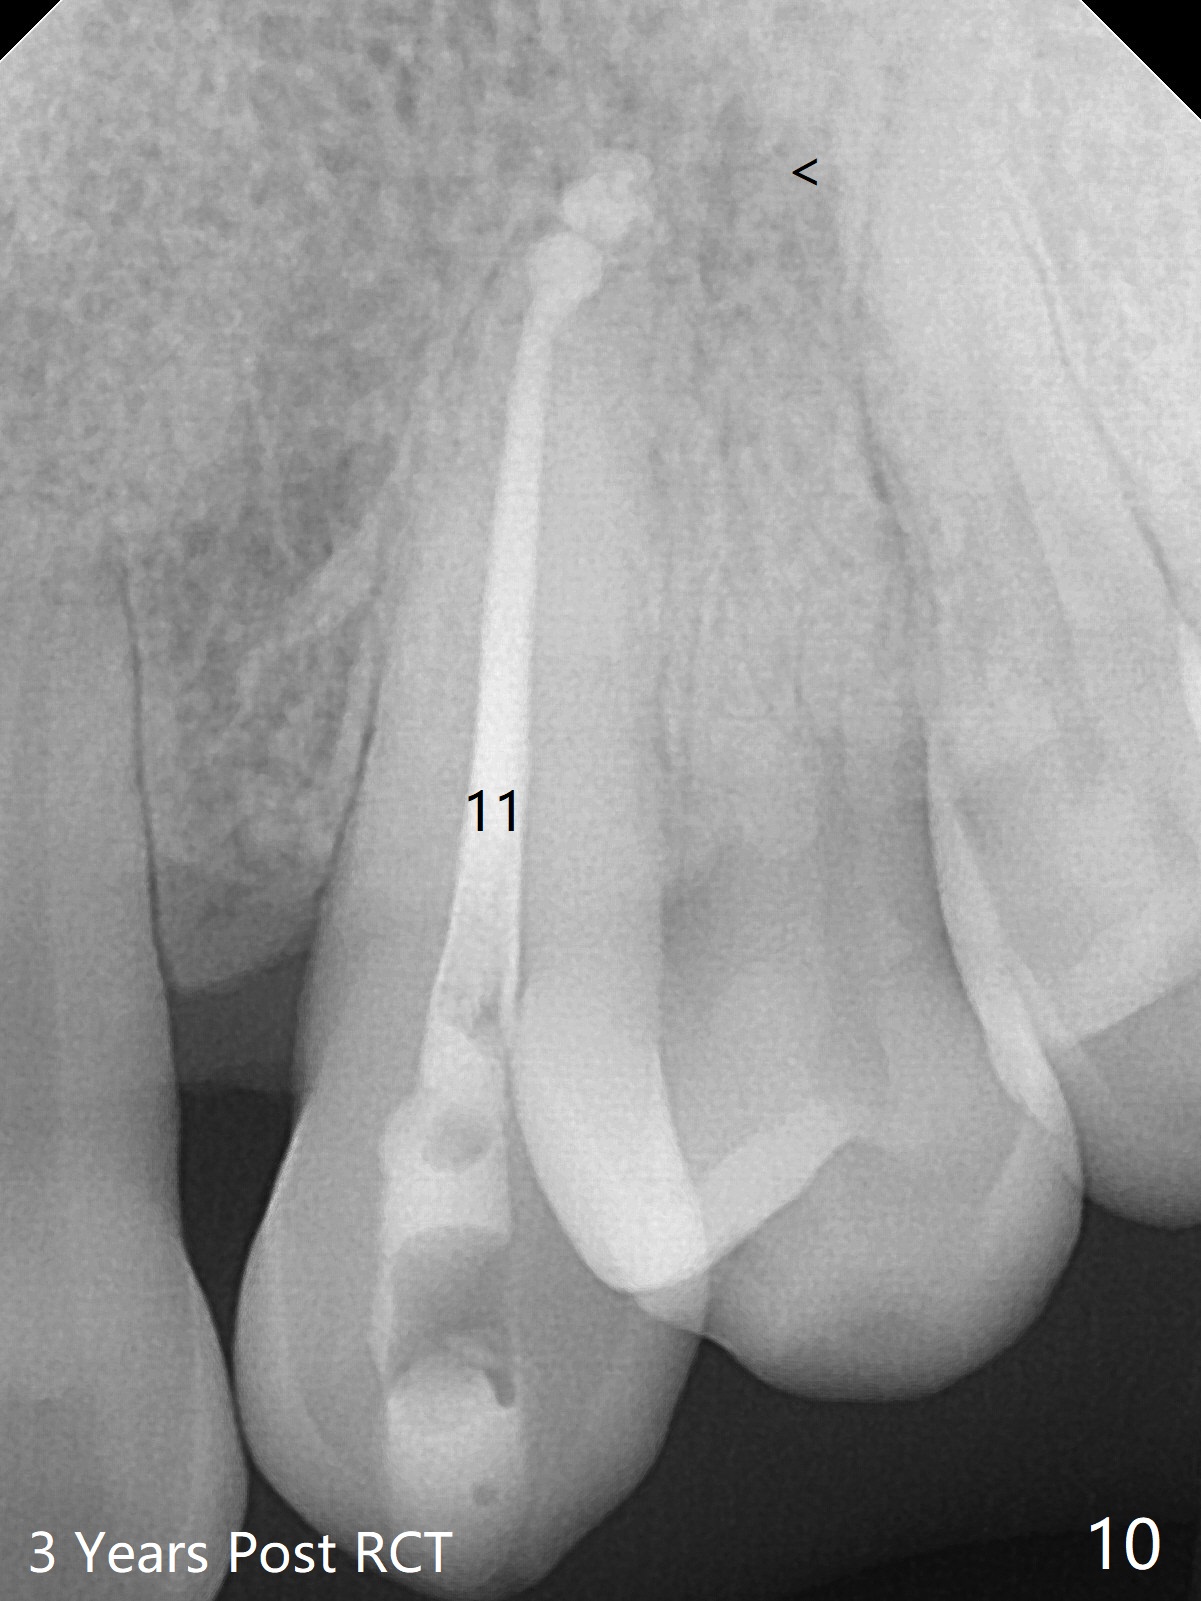

A 45-year-old man had severe malocclusion and chose non-extraction orthodontic treatment (Fig.1 (2012)). Five years later, the tooth #11 discolors (Fig.3, as compared to #6 in Fig.2). Immediately after RCT (Fig.4,5), the affected tooth has sudden change in shade (Fig.6). Two weeks later there is rebound in shade (Fig.7). The latter improves after two rounds of chair-side internal bleaching with 35% Hydrogen Peroxide for 20 minutes and build-up with the lightest shade composite (Fig.8). For optimum, place the bleach gel in the pulpal chamber and close the access with Cavit for a few days. In fact the latter is unnecessary. The treated tooth looks as normal as the tooth on the other side 1 year 10 months post whitening (Fig.9). PARL reduces 3 years post RCT (Fig.10 <, as compared to Fig.5).